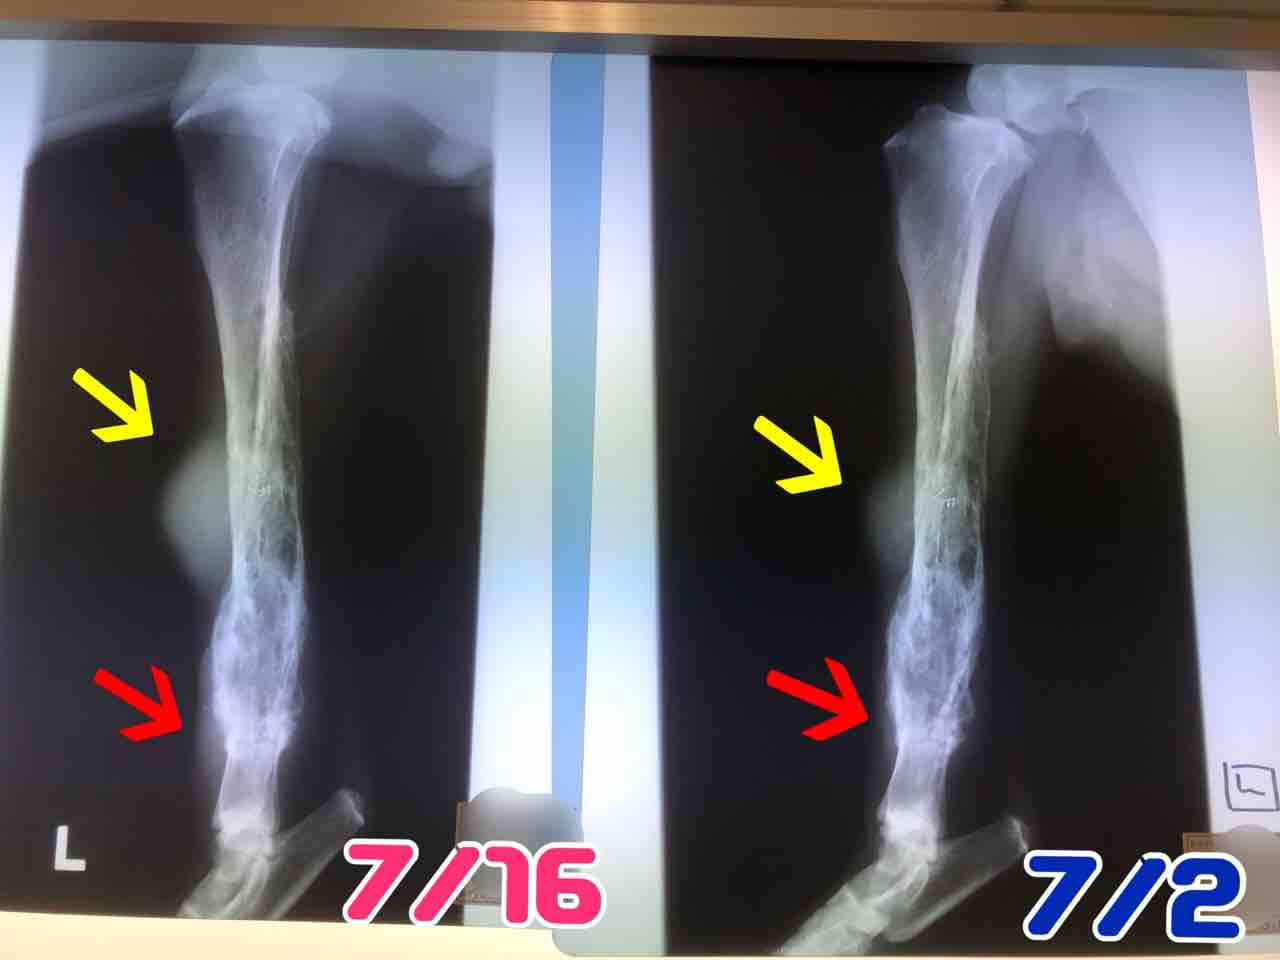

今日は血液検査とレントゲン

バジル

の前脚と後脚、どっちも想像以上に悪くなっていました。

腫瘍の進行が早過ぎます…